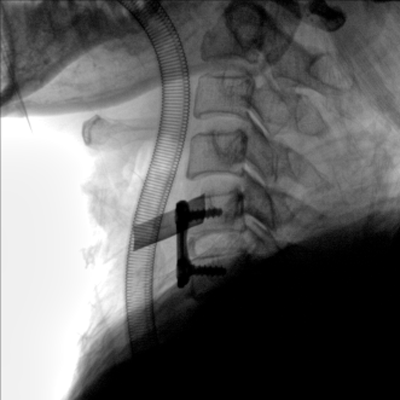

大尺寸動態(tài)平板探測器,高DQE、低噪聲、圖像清晰。采用多分辨率圖像增強處理技術(shù),不同部位不同圖像處理算法,滿足客戶多樣化的需求。

采用智能變頻脈沖透視技術(shù),優(yōu)化圖像質(zhì)量的同時降低輻射劑量,呵護醫(yī)患健康